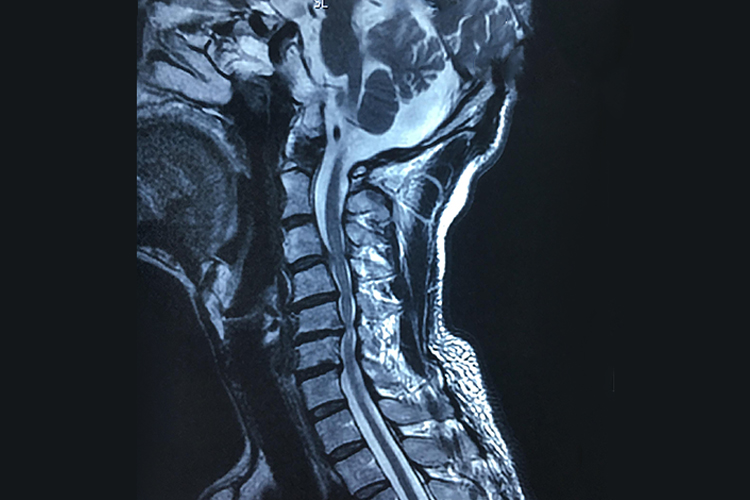

脊髓型颈椎病:颈椎间盘变性,颈椎生理曲度改变,病变椎间隙狭窄,椎体后缘唇样骨赘,椎间孔变小,脊髓受压。